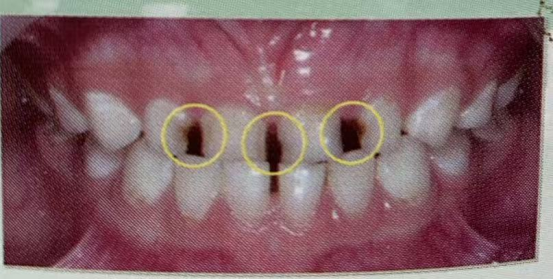

看看下面的这幅图片,您在您的孩子身上见过吗?

龋病:俗称“蛀牙”“虫牙”,是在以细菌为主的多重因素影响下牙体硬组织发生慢性进行性破坏的一种疾病,而我们的牙齿为什么会发生龋病呢?最常见的原因是口腔中的细菌,以日常食品中摄入的糖为食物,代谢产物为酸,酸会腐蚀牙釉质,最终形成龋病,而龋病有哪些危害呢?首先是疼痛,咀嚼能力下降,严重的还会失牙,甚至影响恒牙的健康。随着龋病的进展,当龋坏累及牙髓腔时,就会引发疼痛。乳牙龋有两个典型的特征,第一是发展非常的快,就是当家长发现黑色的时候,往往龋坏已经累积到牙髓。第二是早期自觉症状不明显,即当龋病刚发生的时候,多数儿童不会感到明显疼痛,因此乳牙龋重在预防。龋病的预防由家庭口腔保健和专业口腔保健共同组成,所以家长应该带儿童到医院进行定期的口腔检查。而家庭口腔保健应该注意些什么问题呢?我们再下一个保健内容里再和大家一起分享,祝愿我们的孩子们都拥有一口洁白健康的牙。